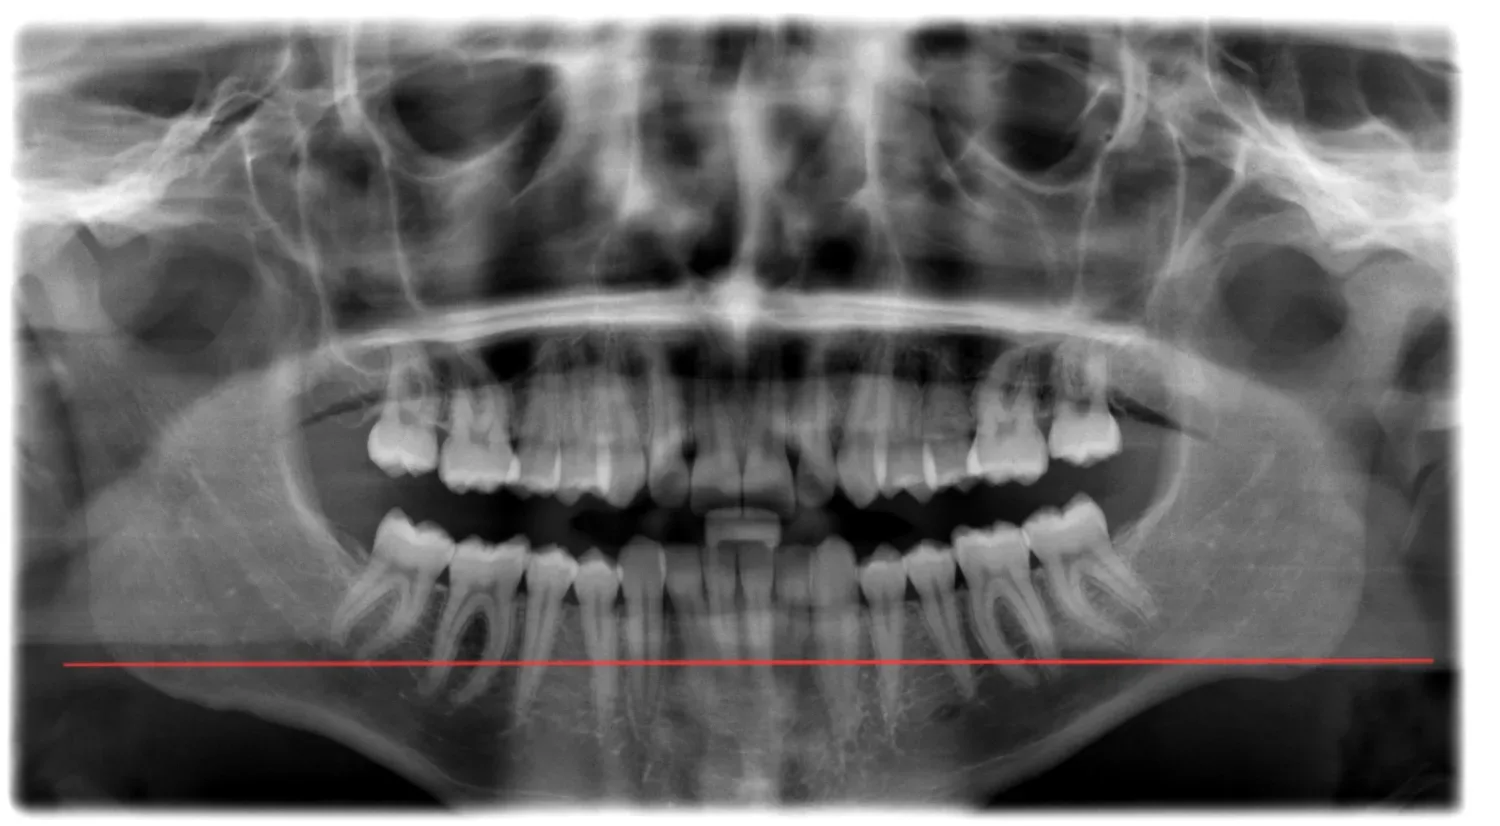

I’m 15.5 with noticeable jaw asymmetry - right ramus is longer than left and a slightly recessed lower jaw. My orthodontist said the it is skeletal and IF i want to correct it i may need jaw surgery (probably a bsso + genio) , but I haven’t been to a maxillofacial surgeon yet since i am 15 and my ortho said that there is no reason to go since they my jaw will still grow.

I’m am not really sure whether I should start braces NOW and get a palate expander (which my ortho said i will need to correct my crossbite and overbite which is likely what caused this, my parents said that they will fully pay for the surgery if i want it once i am 18) or wait until im closer to surgery since I’ll need braces again before and after the procedure anyway and get a palate expander at 18??

Even though it doesnt look that bad in xrays in my opinion the assymetry is noticeable and bsso would benefit me, becouse of my pretty short ramus (atleast it apears so on my left side) and mandible reccession